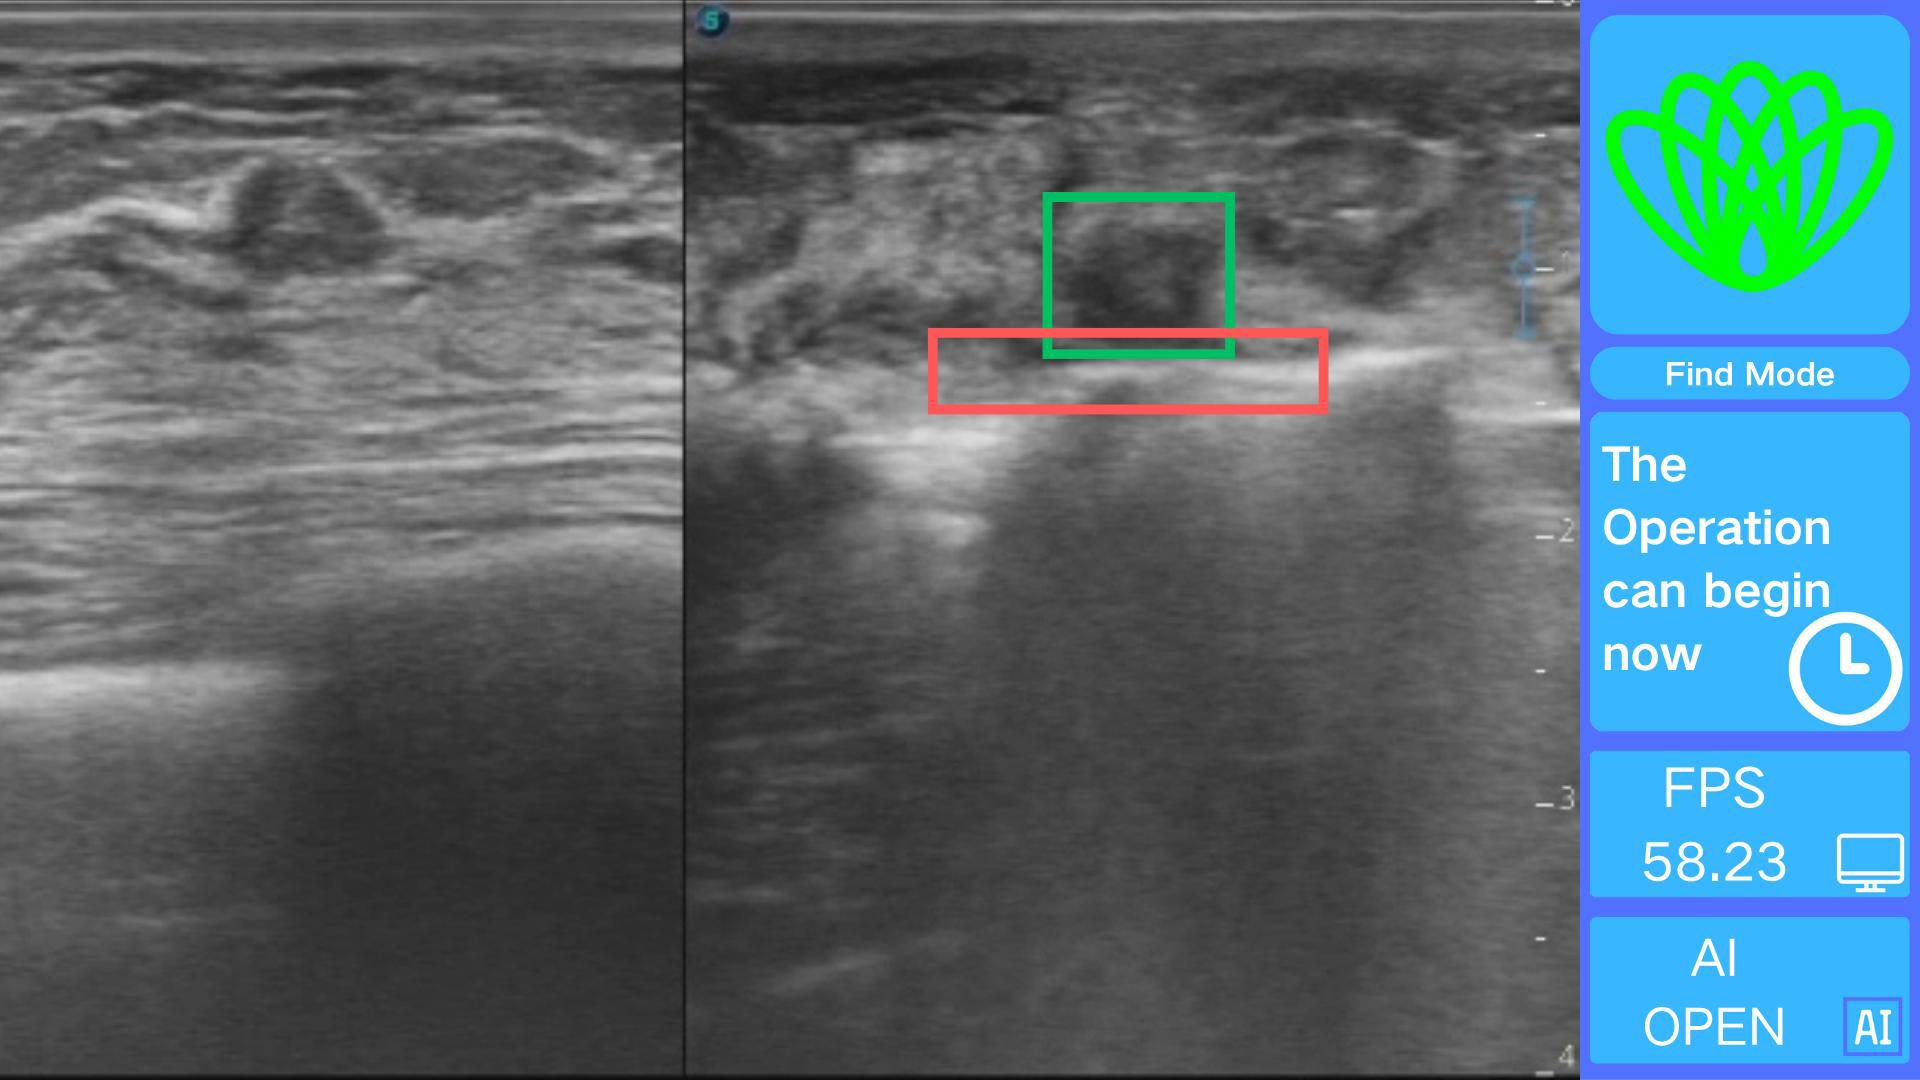

The real-time visualization module creates an interface using OpenCV 4.9.0 for processing real-time ultrasound video streams frame by frame. Each frame is analyzed quickly using the Intel OpenVINO 2025.0.0 toolkit, which adds visually distinct annotations. Based on the cutter slot activation determination method described earlier, a command stating, “The operation can begin now,” is issued, as illustrated in Figure 7.

Figure 7

Ultrasound image divided into two sections. On the left, the green square indicates the detected tumor, and the red rectangle indicates the detected rotational resection tool. On the right, a blue sidebar displays text: “Find Mode,” “The Operation can begin now,” “FPS 58.23,” and “AI OPEN.” A green abstract icon is above the text.

Figure 7. Real-time intelligent guidance interface demonstrating.